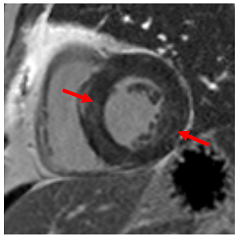

13. Hypertrophic Cardiomyopathy

In clinical practice, the differentiation of hypertrophic cardiomyopathy from hypertensive LVH is a frequent and difficult challenge, especially as the two pathologies frequently coexist. Hypertrophic cardiomyopathy is typically characterised by asymmetrical LVH, usually involving the septum, but any myocardial segment can be involved [54]. Hypertensive LVH often causes concentric LV remodelling, but asymmetrical LVH is not infrequent, and concentric hypertrophic cardiomyopathy is well-described particularly in non-sarcomeric phenocopies (Table 4D), so the pattern of remodelling alone may not be helpful unless it disproportionately affects, for instance, apical segments that do not hypertrophy in isolation in patients with HHD [55,56]. Patients with sarcomeric HCM also frequently develop a reverse septal curvature morphology with a loss of concavity of the septal endocardial surface (Table 4E,F) [57]. Other features that may point towards HCM as opposed to hypertensive heart disease include ancillary abnormalities such as elongation of the anterior leaflet of the mitral valve [58]; protrusion of the anterior leaflet into the LV cavity–26 mm or more (“night cap” mitral valve) [59]; the presence of numerous myocardial crypts [Table 4G] [59] (isolated myocardial crypts are likely within normal limits [60]); apical displacement of the papillary muscles; anteromedial displacement or duplication of the anterolateral papillary muscles; apico-septal muscle bundles (Table 4H) [61]; and accessory papillary muscles or anomalous direct insertion of papillary muscles onto the mitral valve [62]. Systolic anterior motion of the anterior leaflet of the mitral valve and the associated posteriorly directed MR and left ventricular outflow tract obstruction are more frequently seen in HCM than hypertensive heart disease but can occur in both settings, particularly if there is hypertension and isolated basal septal hypertrophy with hyperdynamic LV contractility in the elderly [63]. Some degree of LGE can be seen in approximately two-thirds of patients with HCM, most often in the areas of maximum hypertrophy [64]. The pattern and extent of enhancement are often very heterogeneous within as well as between patients [65]. Diffuse patchy mid-wall enhancement is frequently seen in advanced hypertensive heart disease with poor blood pressure control (Table 4I) but equally can be seen in HCM [47]. However, very dense organised fibrosis is more commonly seen in the latter, particularly in the so-called burned-out phase (Table 4J).